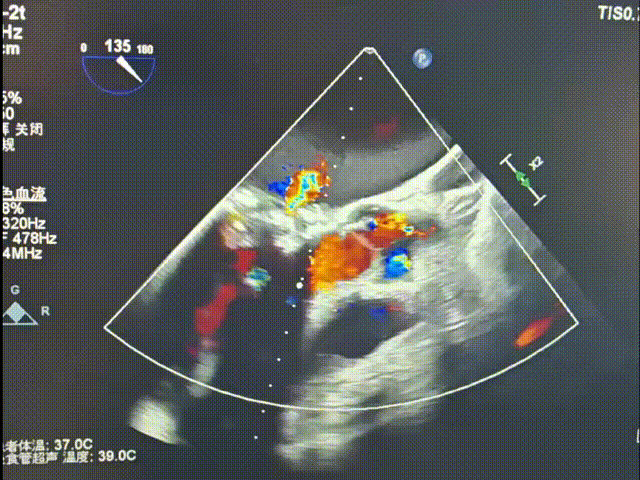

超声提示:

二尖瓣生物瓣置换术后

二尖瓣生物瓣退行性病变狭窄(重度)并反流(轻-中度)

二尖瓣瓣架前缘中等回声(残存腱索可能性大)

左房扩大

三尖瓣反流(轻度)

肺动脉瓣反流(轻度)

肺动脉高压(轻度)

二尖瓣打开通畅,无瓣周漏

二尖瓣

最大流速:104cm/s

平均压差:术前21mmHg→ 术后2mmHg

无需进行球囊后扩张